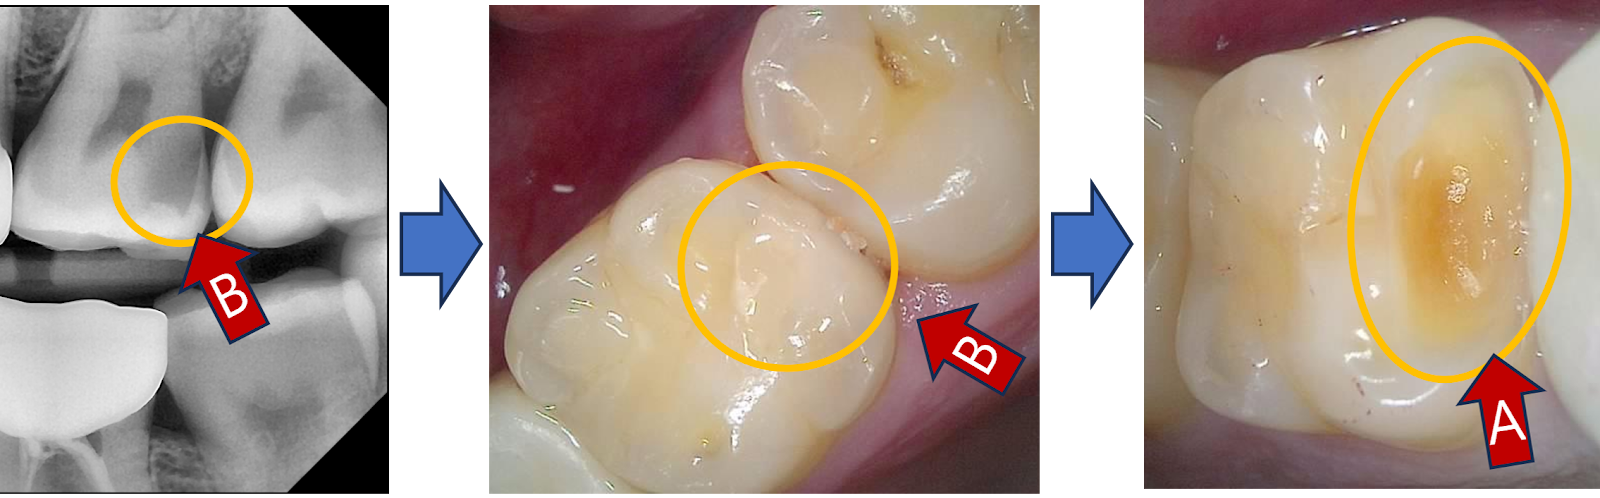

#25의 앞쪽 - #24 방향으로도 충치가 보인다.

#15 검진을 위해 찍었던 CT를 보니, #24에도 (?) 부위에 충치가 의심되는 상황..

인접면 충치 진단, CT로 잘 안 보임

하지만 (?) 부위는 옆에 있는 크라운 때문에 CT로는 정확한 진단이 되질 않는다.

이렇게 옆에 있는 크라운 때문에 CT로 진단이 안 되는 인접면 충치는,

바이트윙(bite wing) - 또는 교익촬영으로 추가 검진을 하면 도움이 된다.

기구를 물고 교익촬영을 해보니, (?) 부위는 다행히 (!)처럼 별 이상이 없어보인다.

바이트윙으로 인접면 충치 진단

빨간 화살표는 양쪽으로 진행된 인접면 우식 확인

그래서 #24는 무죄 판정. 땅땅!

그런데 #25는 인접면 충치가 앞뒤 - 양쪽으로 충치가 진행중이다.